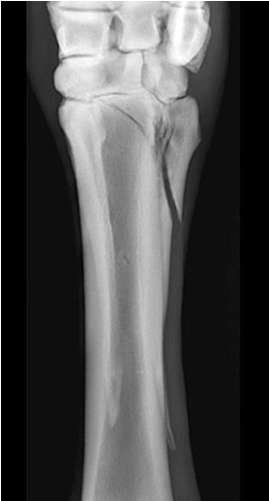

• what view is this?

dorsolateral palmar medial oblique